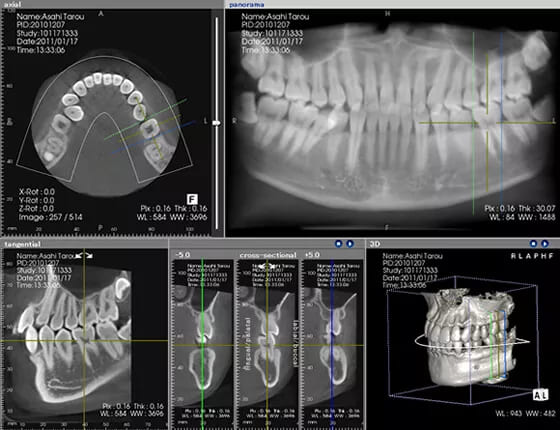

CT診断

顎の状態や噛み合わせの状態を立体的に映し出せる「CT」による診断を行っています。これにより通常の二次元レントゲンよりも精密な診断が可能になります。